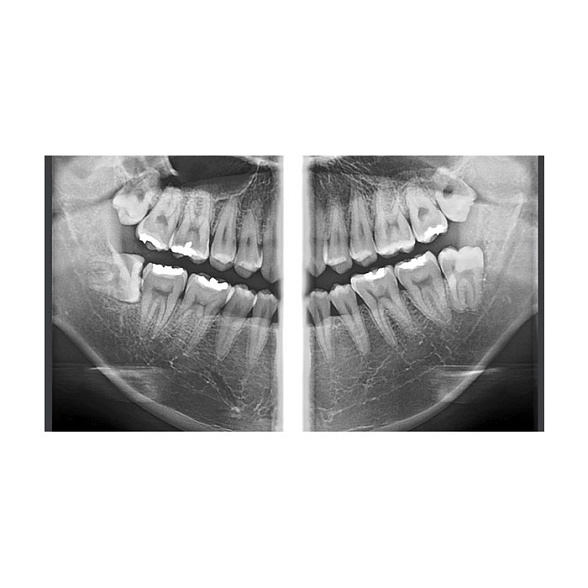

- Высокое качество изображений: Цифровой плоскопанельный детектор обеспечивает высокое разрешение и контрастность снимков, что критически важно для оценки анатомических структур, состояния корневых каналов, положения зачатков зубов.

- Имплантология: Точная оценка объема и плотности костной ткани, планирование позиции имплантатов с учетом важных анатомических структур (нижнечелюстной канал, гайморова пазуха).

- Эндодонтия: Диагностика сложных анатомических особенностей корневых каналов, выявление перфораций, трещин корня, контроль качества пломбирования.

- Пародонтология: Оценка уровня костной ткани при пародонтите.